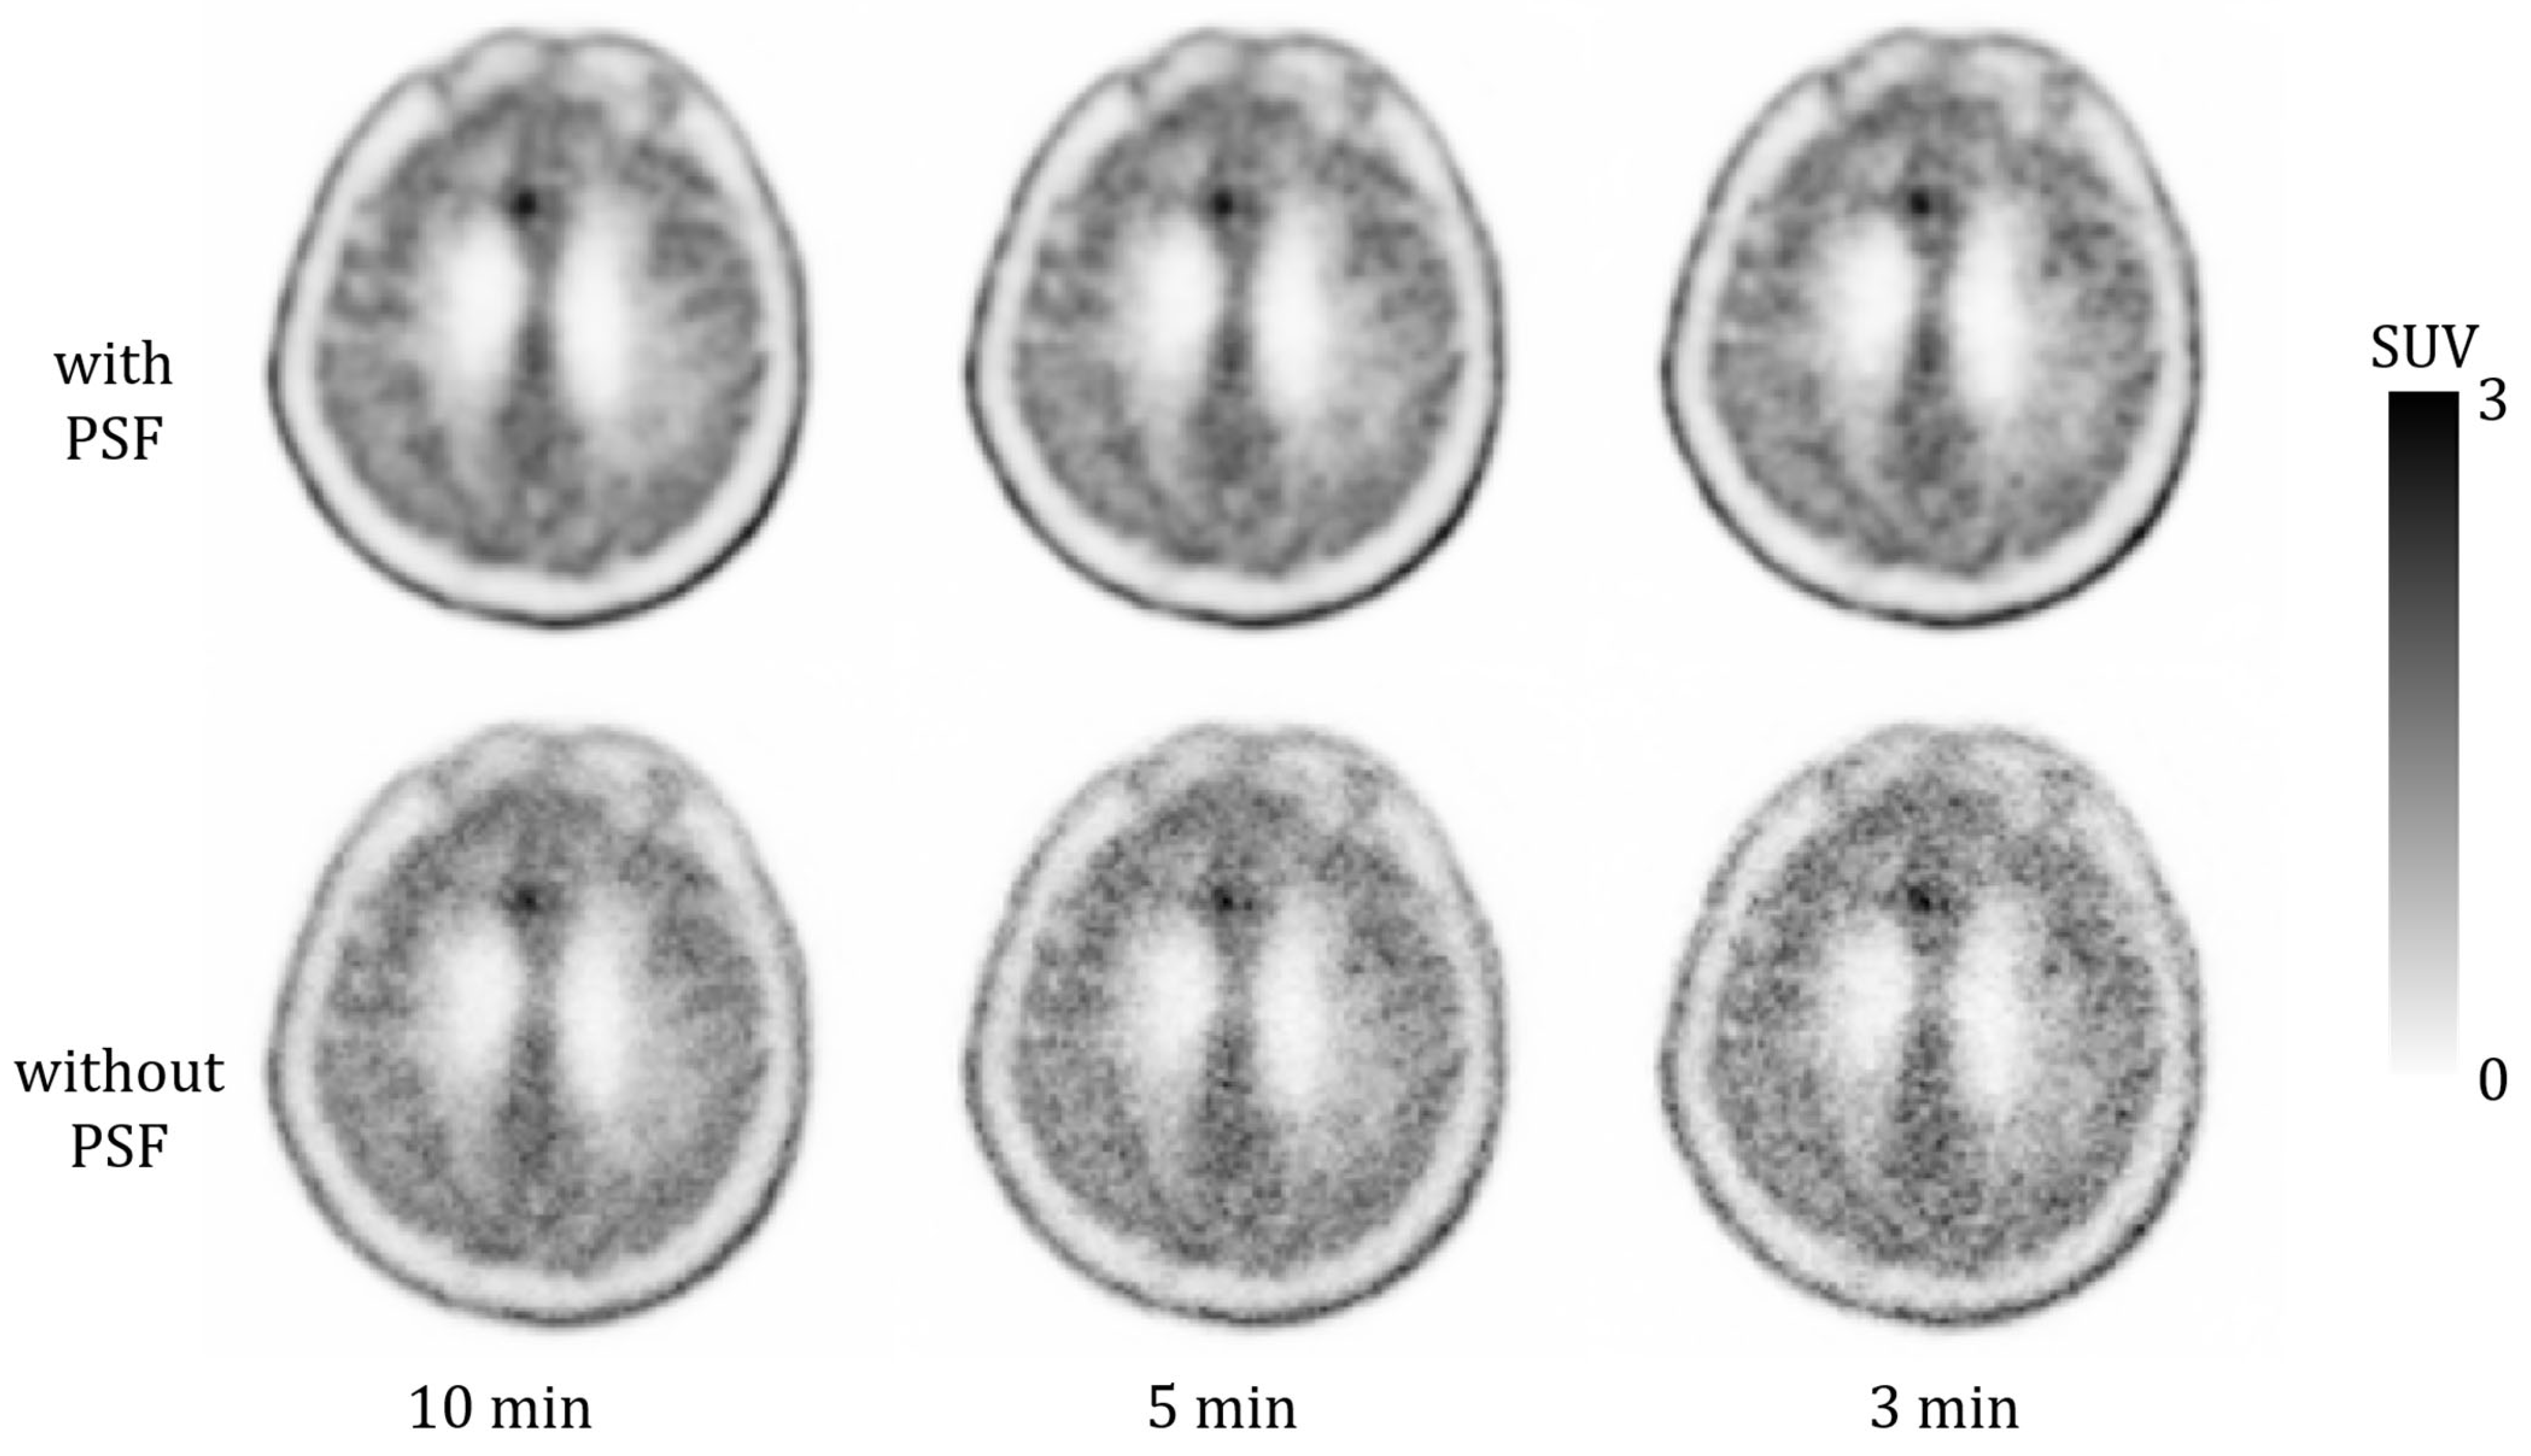

- Reconstruction with PSF: Ordered subset expectation maximization algorithm with PSF correction and time-of-flight (TOF) technique using five iterations and five subsets.

- Reconstruction without PSF: Ordered subset expectation maximization algorithm with the TOF technique using three iterations and five subsets.

| Reconstruction Condition | Acquisition Duration (min) | ||

|---|---|---|---|

| 10 | 5 | 3 | |

| with PSF | 5 | 5 | 5 |

| (range) | (reference) | (4–5) | (3–5) |

| without PSF | 4 | 3 | 2 |

| (range) | (2–5) | (1–5) | (1–5) |